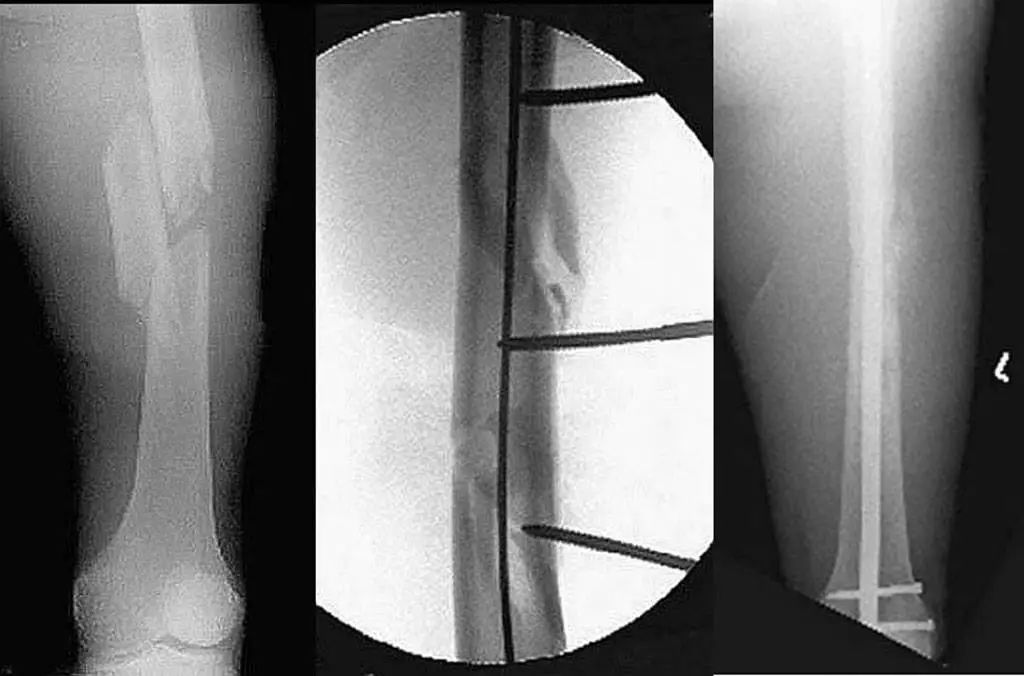

Техника закрытой репозиции может помочь в выравнивании перелома ножки бедренной кости без повреждения мягких тканей или кровоснабжения конца перелома и может использоваться для внутренней фиксации с помощью интрамедуллярного стержня.

Под эпидуральной анестезией больной ложится плашмя на койку (кожа пораженной конечности в это время не стерилизована), один ассистент держит икру пораженной конечности, а другой ассистент салфеткой оттягивает корень бедра пациента ремень для противодействия вытяжению, при этом пораженная конечность находится в нейтральном положении, а коленная чашечка обращена вверх (перелом ножки бедренной кости обычно не ротируется и не смещается при натяжении мышц и может быть исправлен автоматически путем вытяжения, поэтому оператору требуется только исправить переднезаднее и боковое смещение сломанного конца ножки).

Оператор использует обе руки, чтобы обхватить пораженную конечность и держит руки вместе (рис. 3 и рис. 4), и одновременно исправляет передне-заднее и боковое смещение перелома, используя косую зажимную силу обоих предплечий.

Например, если проксимальный сегмент перелома бедренной кости смещен кнаружи и кпереди, одно предплечье используется для сжатия проксимального сегмента перелома внутрь и вниз.Другое предплечье сжимает дистальный сегмент перелома наружу и вверх, чтобы позаимствовать усилие зажима (врач, выполняющий вправление, должен правильно оценить направление смещения перелома и расстояние смещения перед повторным вправлением), чтобы перелом можно было успешно вправить за один раз.В процессе репозиции ассистент должен увеличить силу вытяжения и не допускать вращения бедренной кости.

Когда конец перелома в основном притерт, должен быть слышен слабый звук трения кости, в это время ассистент должен по-прежнему поддерживать тракцию, но уменьшать силу тракции.

Когда перелом в основном выровнен с помощью аппарата С-дуги (если небольшое смещение все еще есть, внесите некоторые коррективы, чтобы убедиться, что концы перелома совпадают друг с другом), сохраняйте тракцию, продезинфицируйте пораженную конечность и расстелите полотенце, а затем выполнить интрамедуллярную фиксацию гвоздями.

Для пациентов с большим смещением перелома, неудачными закрытыми манипуляциями или оскольчатыми переломами хирургическая тракционная кровать может использоваться для закрытой репозиции с некоторой инструментальной силой, которая также может эффективно завершить закрытую репозицию перелома ножки бедренной кости.

После размещения пораженной конечности на тракционной раме для вытяжения и осмотра С-дуги, показывающего, что смещение перекрывающихся переломов было скорректировано, дистальный конец пораженной конечности можно скорректировать внутрь для дальнейшего восстановления выравнивания и выравнивания в ортостатическом изображении бедренный ствол.

Поскольку напряжение мышц бедра при тракции может играть роль шинирования мягких тканей при переломе ножки бедренной кости, большинство переломов ножки бедренной кости могут получить более удовлетворительное выравнивание на ортогональном рентгеновском изображении.

Однако в настоящее время из-за отсутствия эффективной опоры на дистальном конце переломного сегмента под действием силы тяжести дистальный переломный сегмент ножки бедренной кости в основном смещается кзади, и в это время стерильная махровая салфетка На заднюю сторону дистального конца перелома после стерилизации, подготовки кожи и укладки стерильных пластырей можно наложить ортез, а заднее смещение дистального конца перелома можно исправить, регулируя высоту ортеза.

Если заднее смещение дистального сегмента перелома еще не устранено, проксимальный стержень может быть установлен чрескожно на верхушке большого вертела или грушевидной ямке, а затем в костномозговую полость проксимального сегмента перелома вводится интрамедуллярный репозиционный стержень. бедренной кости, а рукоятку интрамедуллярного репозиционирующего стержня умеренно поднимают вперед, чтобы отжать проксимальный перелом бедренной кости назад с помощью рычага репозиционного стержня, тем самым восстанавливая совмещение со смещенным кзади дистальным переломом,

После совмещения перелома в дистальную полость перелома вводят длинный направляющий штифт для завершения закрытого вправления.Интрамедуллярный репозиционный стержень особенно эффективен при коррекции деформаций сгибания, отведения и наружной ротации, характерных для проксимальных переломов проксимального отдела бедренной кости (рис. 5).

Для остаточного бокового смещения отверстие изогнутого конца интрамедуллярного стержня можно отрегулировать, чтобы направить длинный направляющий штифт в дистальную полость перелома для завершения закрытой репозиции.

Другой метод закрытой репозиции заключается в том, чтобы ввинтить стержень Шанца в кортикальный слой кости на стороне смещенного конца перелома и скорректировать конец перелома с помощью стержня Шанца для закрытой репозиции (рис. 6).После удовлетворительного совмещения перелома интрамедуллярный стержень вводят в проксимальную и дистальную костномозговую полость перелома для завершения внутренней фиксации (рис. 7).